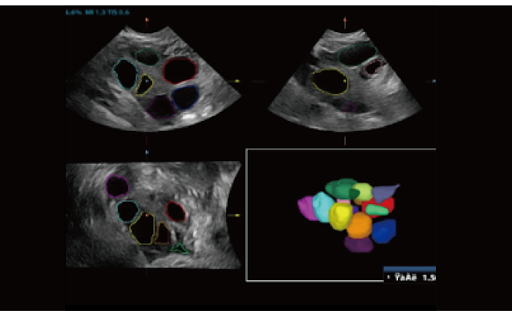

Тканевой трекинг